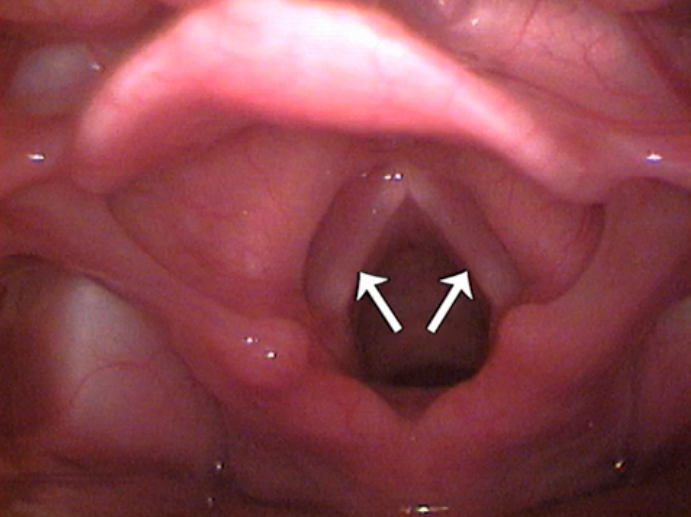

Which structures are being indicated here?

Vocal folds